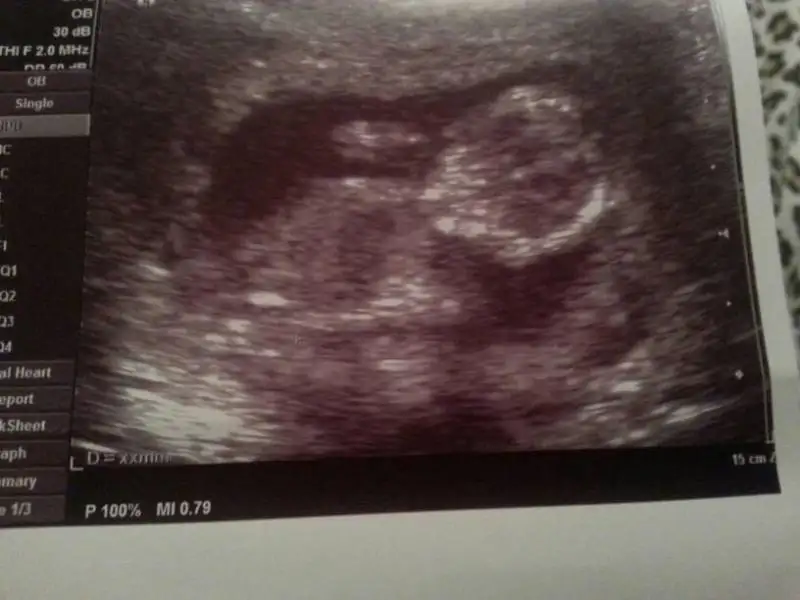

Selam kizlar. Ben de dun gittim doktora ikili icin.

Bizim inatci keçi gostermedi ensesini.

Ilk gittigimizede uyuyordu. Yuru gel dedi doktor.

Ciktim meyve suyu ictim yürüdüm geldim bizim ki hop hop hoplamaya basladi sok olduk.

Beklemiyorduk bu kadar hareket.

Bir de 12 haftalik bekliyordum 13 haftaoik ve günuyle uyumlu cikti :)

Depar atmis bizimki gününü yakalamis :)

Tam 25 dk enseyi aradik doktor tam vazgececekti ki yakaladi olctu 0.7 mm cikti.

Kan sonucu dabir hafta sonra cikacakmis. Uğraştirdi doktoru ama biz mutlu mesut hoplamasini izledik eşimle. Cok guzeldi... bir ara elini basina götürdü asker selami cakti bize...